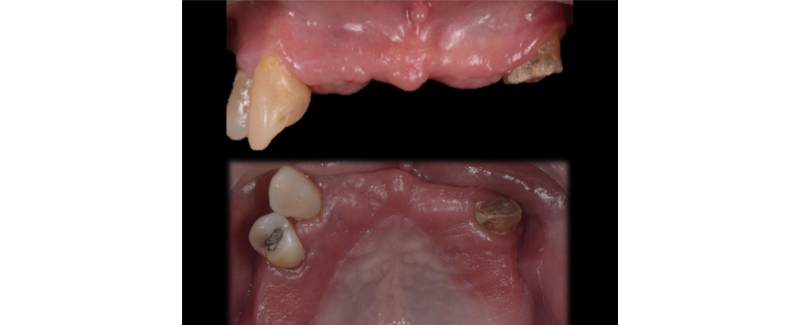

1. Advanced structural damage (Fig. 1)

2. Advanced periodontal damage. (Fig. 2)